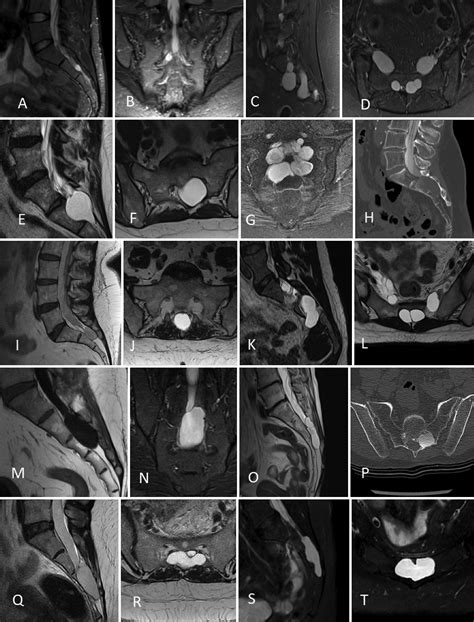

Diagnosing a symptomatic Sacral Tarlov Cyst requires a comprehensive approach. Because they are soft-tissue structures, they are best visualized using high-resolution Magnetic Resonance Imaging (MRI). A radiologist or neurosurgeon will look for specific markers, such as the location, size, and the degree of bone remodeling (erosion) occurring in the sacrum, which indicates that the cyst has been present for a significant period.

In addition to imaging, physicians may conduct a detailed neurological examination to map out sensory deficits and assess muscle strength. Some clinics may also utilize specialized imaging, such as a Cine-MRI, to study the flow of cerebrospinal fluid around the cyst.

A Sacral Tarlov Cyst, also known as a perineural cyst, is a cerebrospinal fluid-filled sac that develops at the junction of the dorsal root ganglion, most commonly in the sacral region—the triangular bone at the base of the spinal column. These cysts are formed when cerebrospinal fluid (CSF) enters the nerve root sheath and becomes trapped, creating a structural abnormality that can press against the delicate nerve fibers housed within the spinal canal.

Because these cysts often remain asymptomatic, they are frequently discovered incidentally during diagnostic imaging, such as an MRI or CT scan performed for an unrelated reason. However, when they grow in size or exert significant pressure on the surrounding nerves, they can lead to a variety of symptoms that mimic other spine-related conditions, making an accurate diagnosis essential.